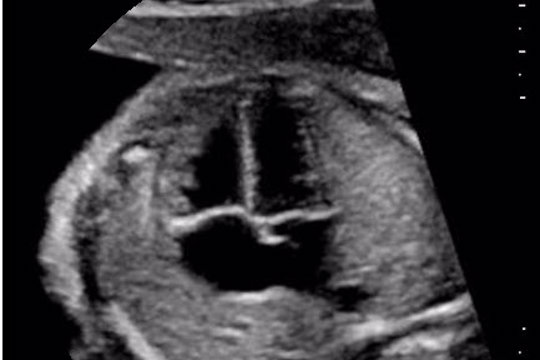

Fetaler Echo-Abschlusskurs

D1/2025 - Fetale Echokardiografie Kursreihe 2025